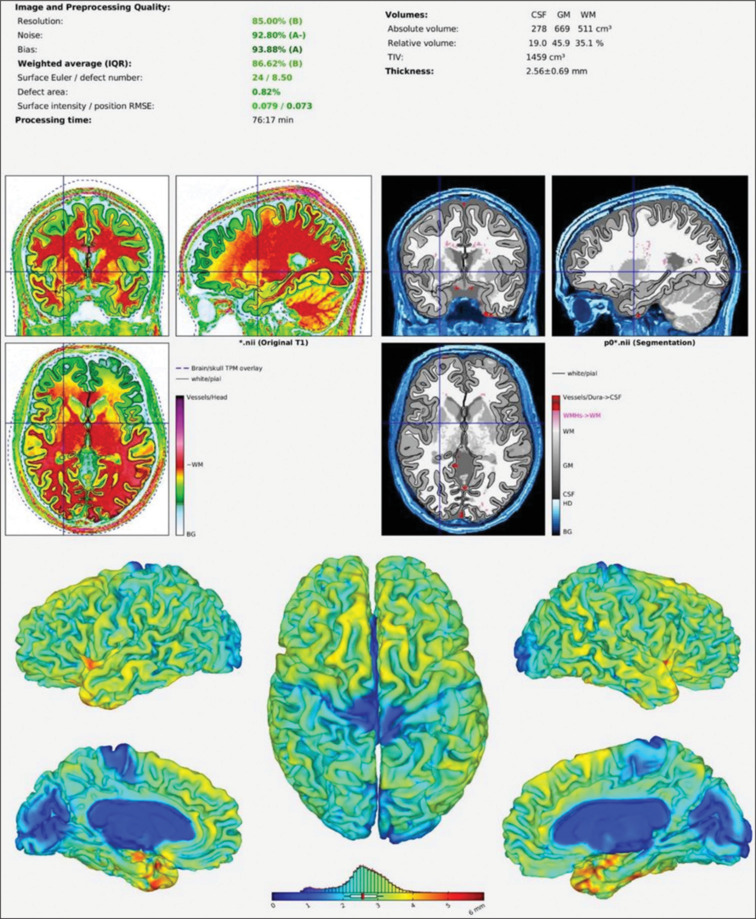

Materials and methods: This cross-sectional study included 222 participants aged 18-60 years, categorized into four groups based on BMI and physical activity levels. Brain MRI scans were acquired using a 3-Tesla scanner. Volumes of various brain regions were calculated and normalized to total intracranial volume. One-way ANOVA and Games-Howell post-hoc tests were used to analyse differences across groups.